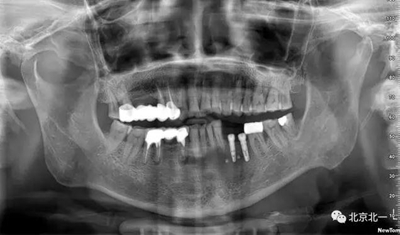

患者術(shù)前片, 最窄骨寬度僅僅3mm,34-35牙位缺失,

CBCT顯示如下圖